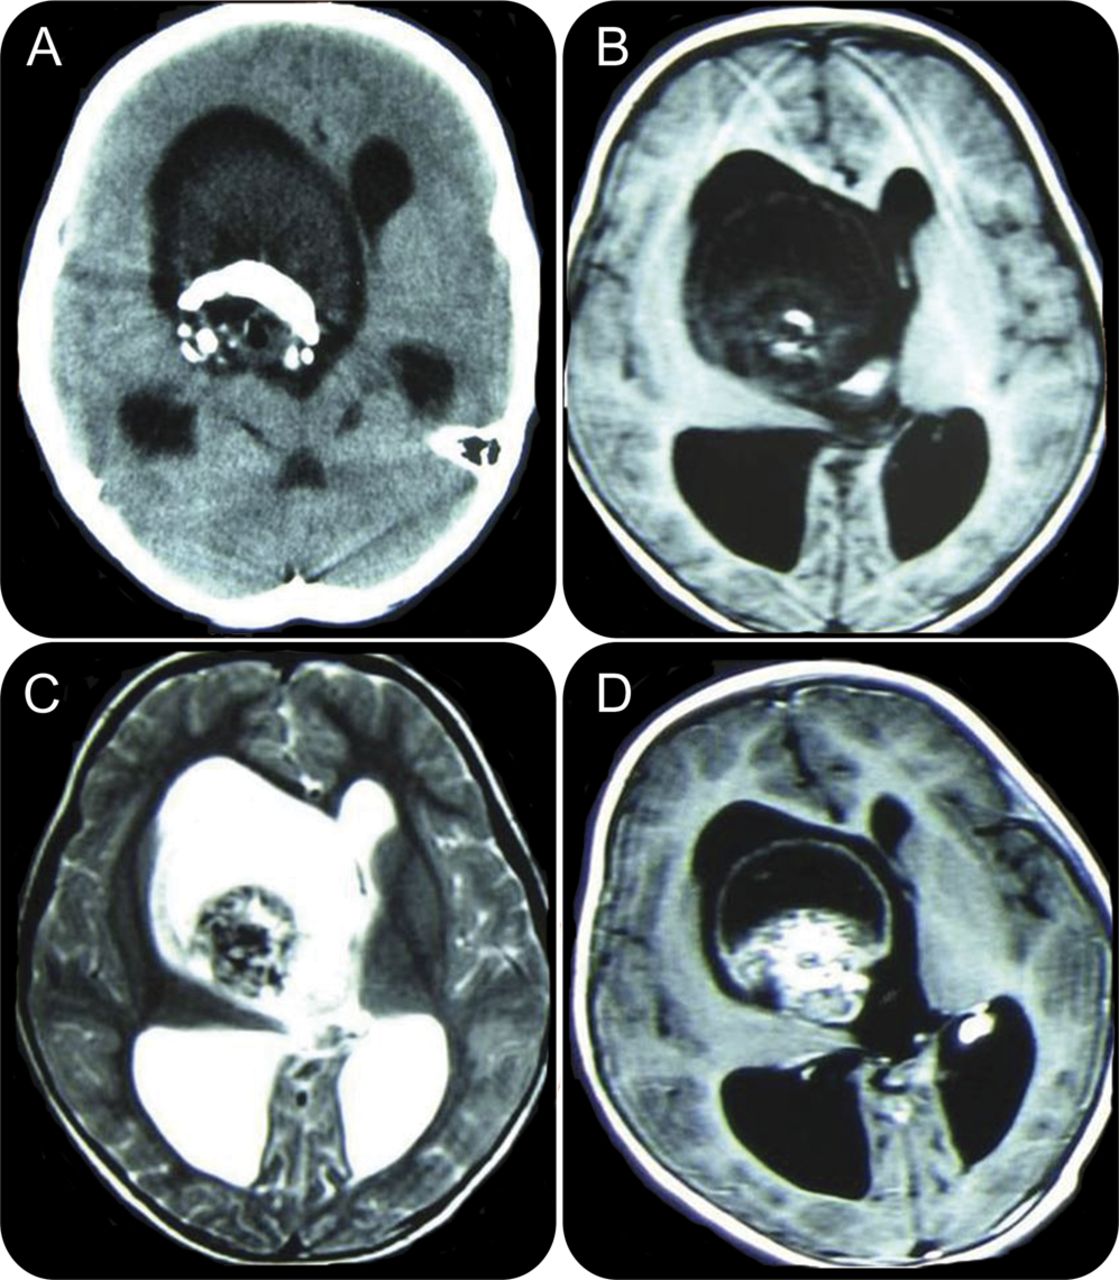

图1

脑CT和核磁共振

轴向CT扫描显示了一个质量与非均匀密度和巨大的钙化病变对侧脑室(a),颅磁共振t1轴向(B)和T2-weighed轴向(C),显示了一个软组织肿块和高信号强度较低。超声造影图像显示病变(D)的异构增强。